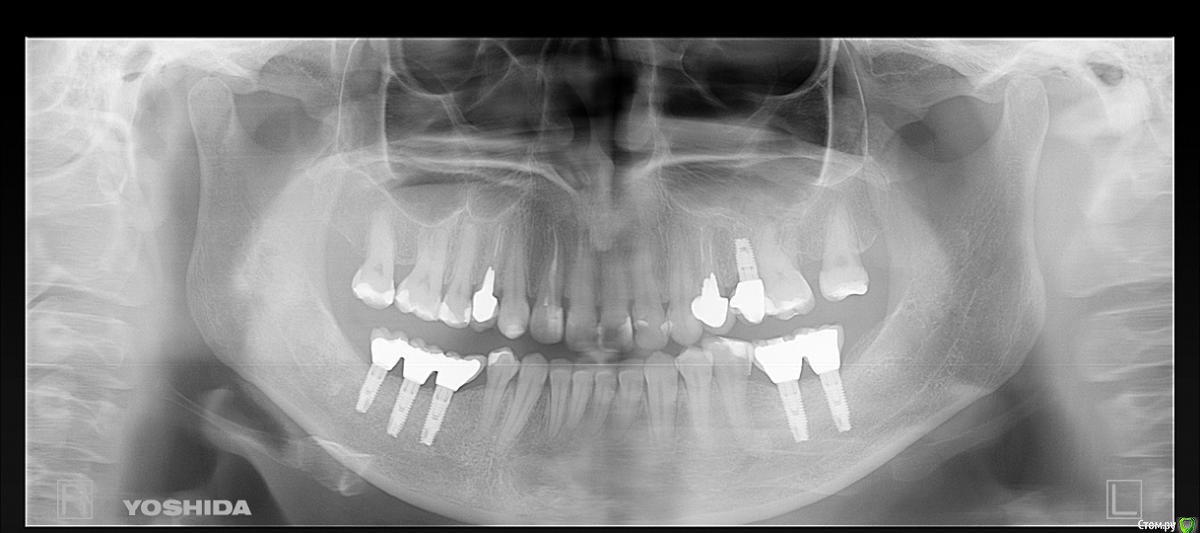

Таня-К Опубликовано 21 декабря, 2014 Поделиться Опубликовано 21 декабря, 2014 Добрый день, уважаемые врачи! Прошу Вашей консультации по имплантам. Импланты установлены в ноябре 2012 года, запротезированы в апреле 2013 (снимок 1 сделан в августе 2013). В октябре 2014 заменены коронки с целью улучшения окклюзии и эстетики, поскольку были мышечные боли и парафункции. Снимок 2 - новое протезирование.Проконсультируйте, пожалуста, произошла ли резорбция десны вокруг имплантов слева (там где три) и существует ли на данном этапе угроза для имплантов? Ссылка на комментарий